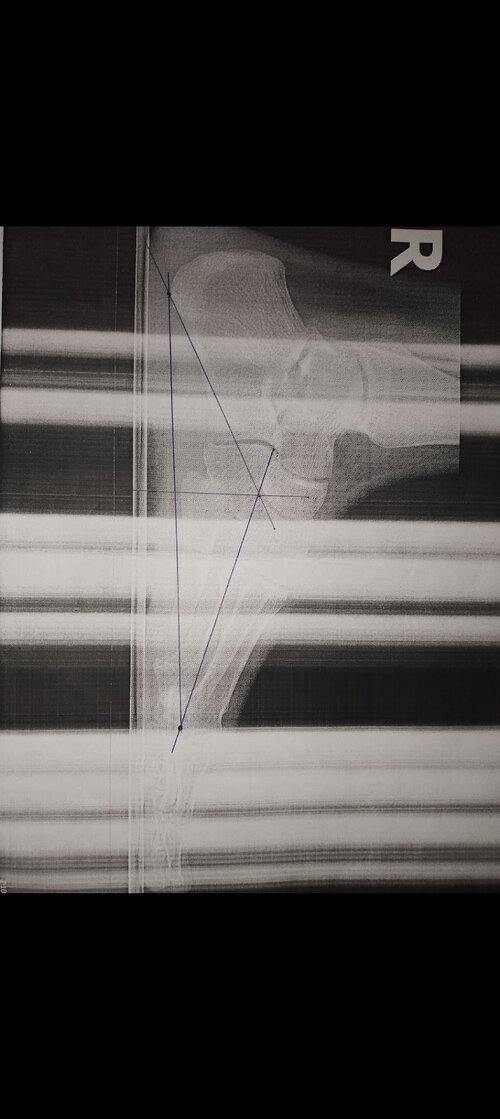

Are my growth plates open or closed? (Sorry for the bad picture) I'm 17 years old, 173cm tall, haven't grown a centimeter since I was 14, help

• Screenshot_20260105-232318.jpg

Screenshot_20260105-232318.jpg